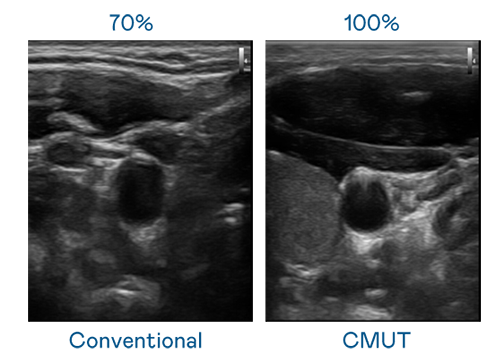

CMUT 技術是一種用電容式微機電元件來產生超音波訊號的技術。與傳統 PZT 壓電式技術相比,CMUT 頻寬增加 30%,更寬頻的超音波訊號讓影像解析度大幅提升,是實現高影像品質醫療超音波掃描、促進精準醫療發展的關鍵技術。

大頻寬帶來超清晰影像

超音波影像的解析度高低,首先取決於探頭能發出的訊號頻寬。AG百家乐 CMUT 可提供高清晰的超音波訊號,提供高頻寬、高靈敏度、影像紋理細節更高的超音波影像,協助醫護人員縮短影像判讀時間及利用精準的醫療影像進行診斷。